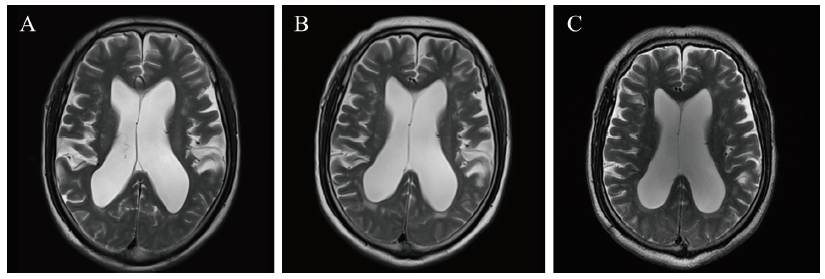

图1 一例AAV肾损害合并交通性脑积水患者的颅脑MRI T2加权像

注:A为2019年3月7日MRI结果;B为2020年7月2日MRI结果;C为2021年8月2日MRI结果;双侧脑室周围白质可见散在多发斑片状FLAIR高信号影,部分融合成片,双侧侧脑室扩大、变钝,中线结构居中未见移位,提示交通性脑积水,双侧放射冠多发缺血、梗死灶,脑萎缩。

自2019年3月至撰稿日,共随访30个月。患者出院后继续口服泼尼松30 mg/d治疗原发病,并逐渐减量至10 mg/d维持。患者共行12次环磷酰胺冲击治疗(每次0.4~0.8 g),累积剂量7.2 g。在我院住院期间反复查颅脑MRI,结果提示双侧幕上脑白质多发缺血灶、幕上脑室系统扩张、脑萎缩较前相仿(图1B、C)。患者目前仍有双下肢酸痛,头晕、行走不稳好转,智力未进一步减退。2021年8月复查血清肌酐为335 μmol/L,血尿素氮14.7 mmol/L,MPO 32 U/L,p-ANCA (-),尿红细胞(-),尿蛋白定量0.803 g/24 h。